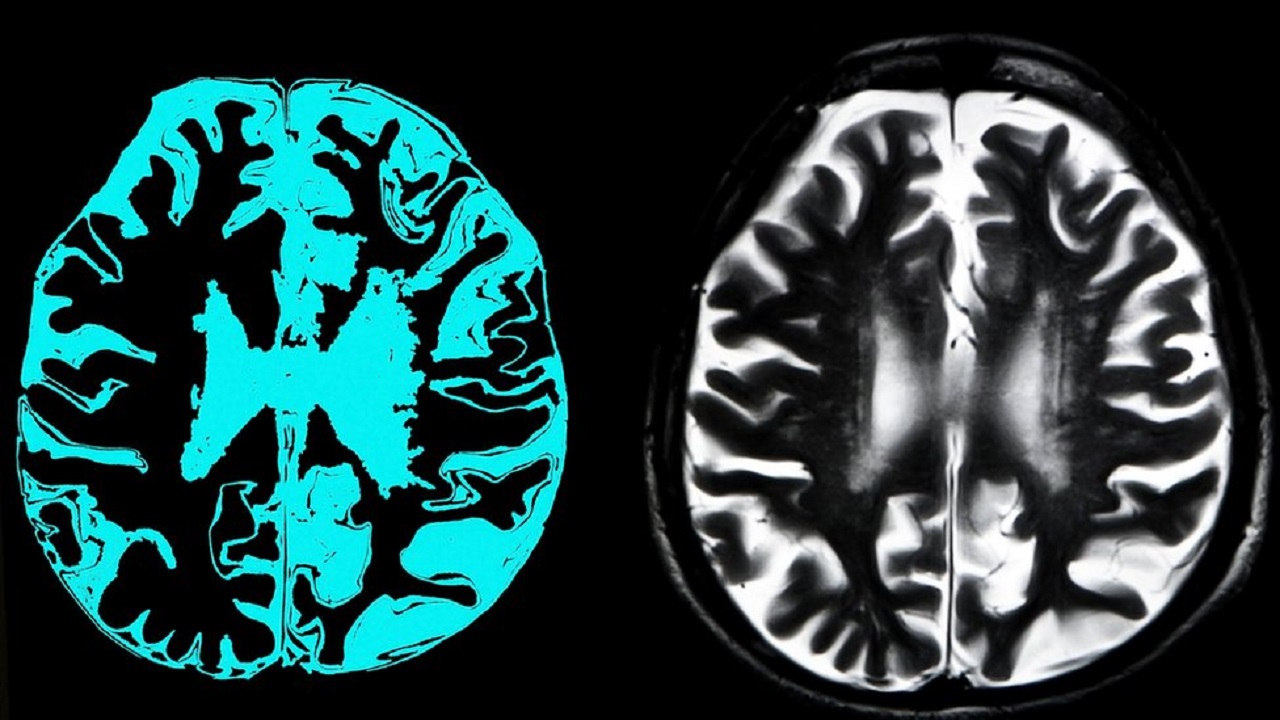

এক বিবৃতিতে বলা হয়েছে, নতুন এই ওষুধটি মস্তিষ্কে আলঝেইমার সৃষ্টিকারী এক ধরনের প্রোটিন কমাতে সক্ষম।

অ্যাডুকেনুম্যাব নামের ওষুধটি উদ্ভাবন করেছে মার্কিন প্রতিষ্ঠান বায়োজেন। আলঝেইমার রোগে যথাযথভাবে কাজ না করায় ২০১৯ সালের মার্চে এর ট্রায়াল স্থগিত করা হয়েছিল। মস্তিষ্কের রোগ প্রতিরোধের তুলনায় ওষুধটির পার্শ্বপ্রতিক্রিয়ার মাত্রা নিয়েও সমালোচনার মুখে পড়ে বায়োজেন।